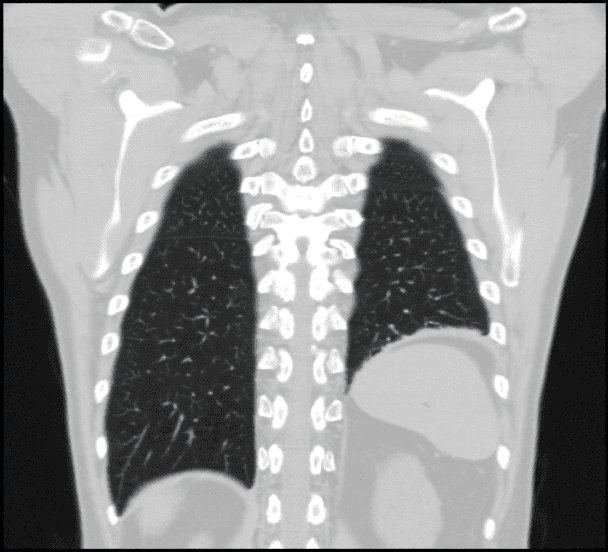

Corrección de la parálisis diafragmática

Se realiza plicatura del diafragma paralizado por causa conocida o idiopática.